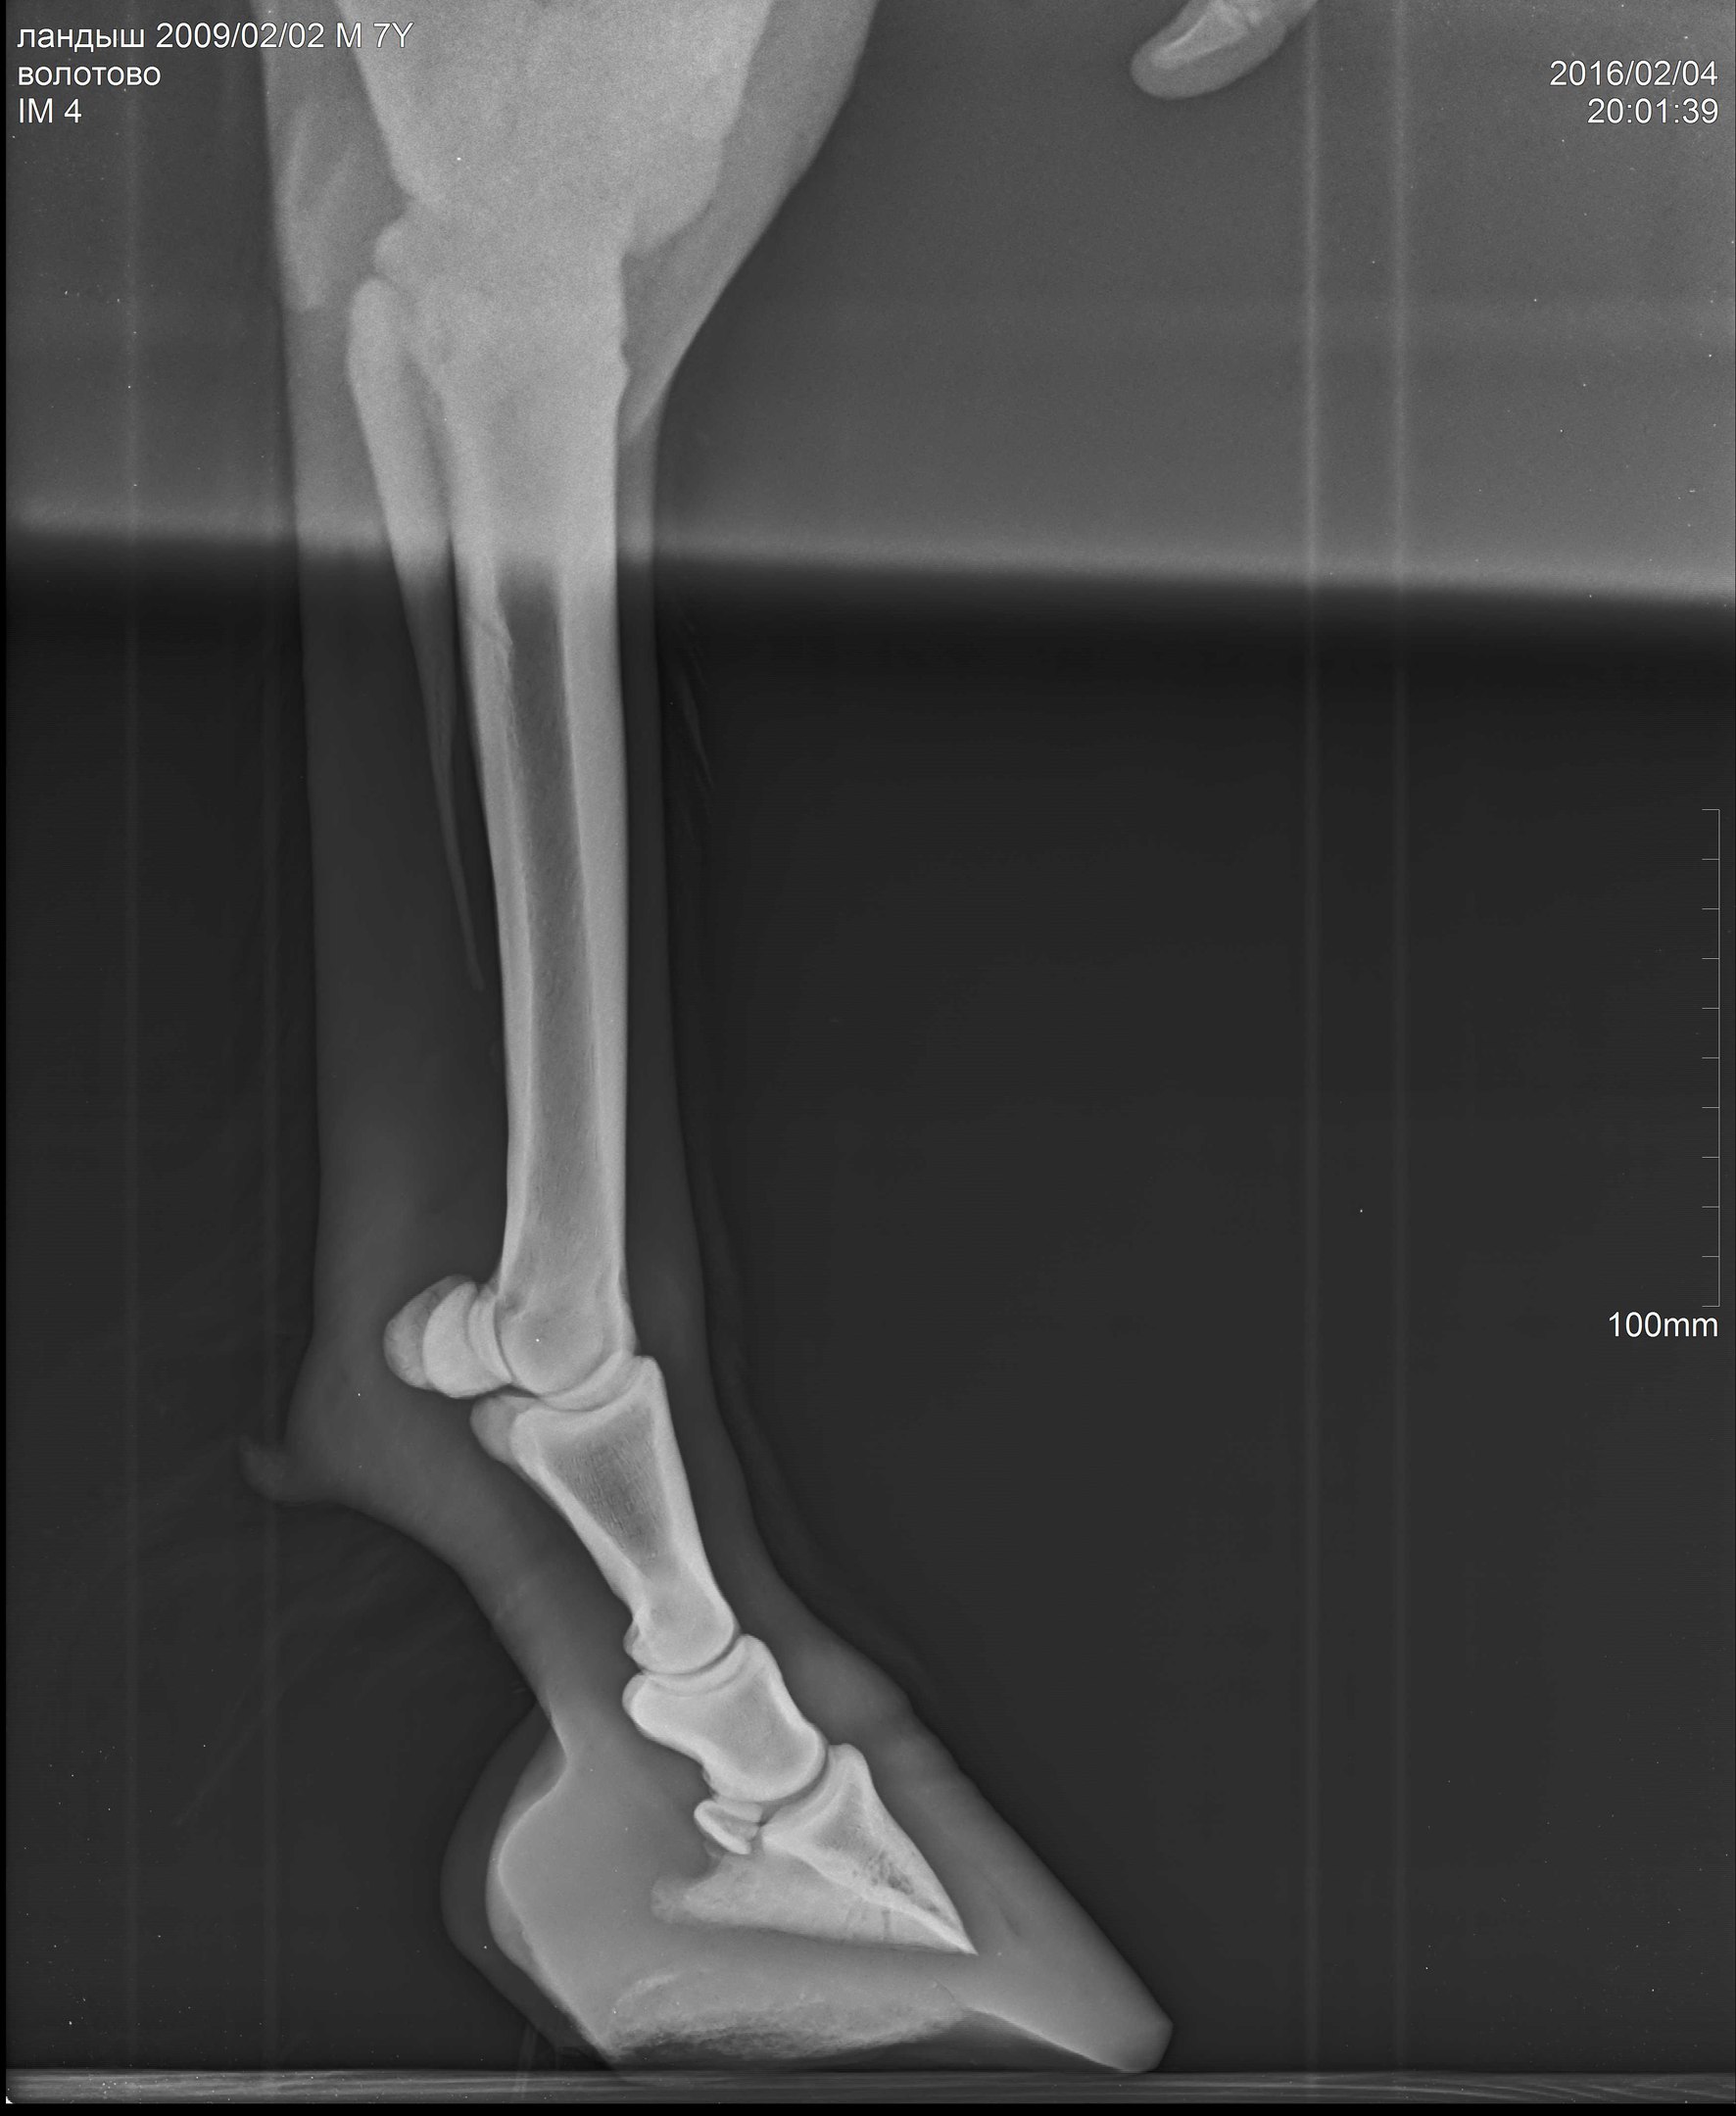

В общем, после чудесного-расчудесного лекарства Флуниджекта и замечательных обнадеживающих рентгенов пони всего лишь требовалась грамотная расчистка. Нужно было чуть изменить угол копыт, чтобы выправить копытную кость более-менее параллельно подошве (хоть в некоторых статьях я читала, что совсем необязательно эта параллельность должна быть нормой).

А тут нужна была тонкая, филигранная работа. Рентгенолог Анна мне оставила диск с программой, где можно было выверять углы, каждый миллиметр контролировать!!!! А я, конечно, со своими клещами и целью тупо на 1см понизить пятки, натворила дел (((